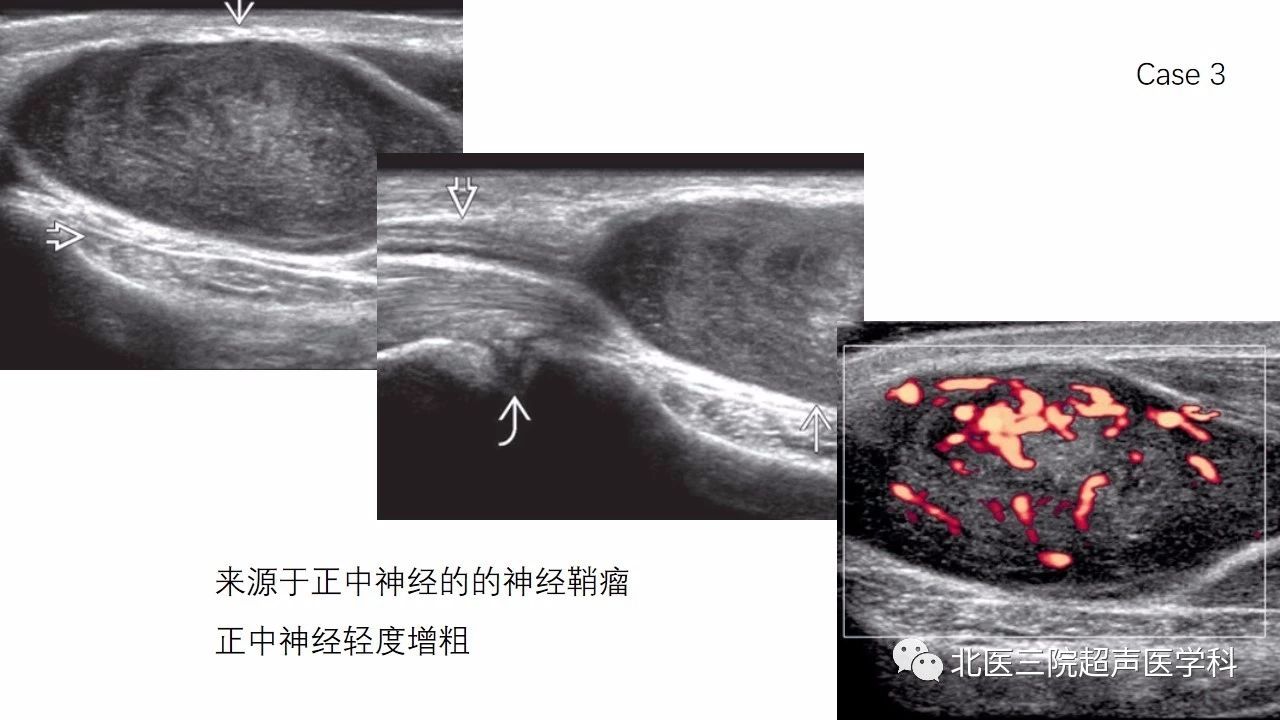

【经典超声书籍解读】周围神经肿瘤性病变(上)